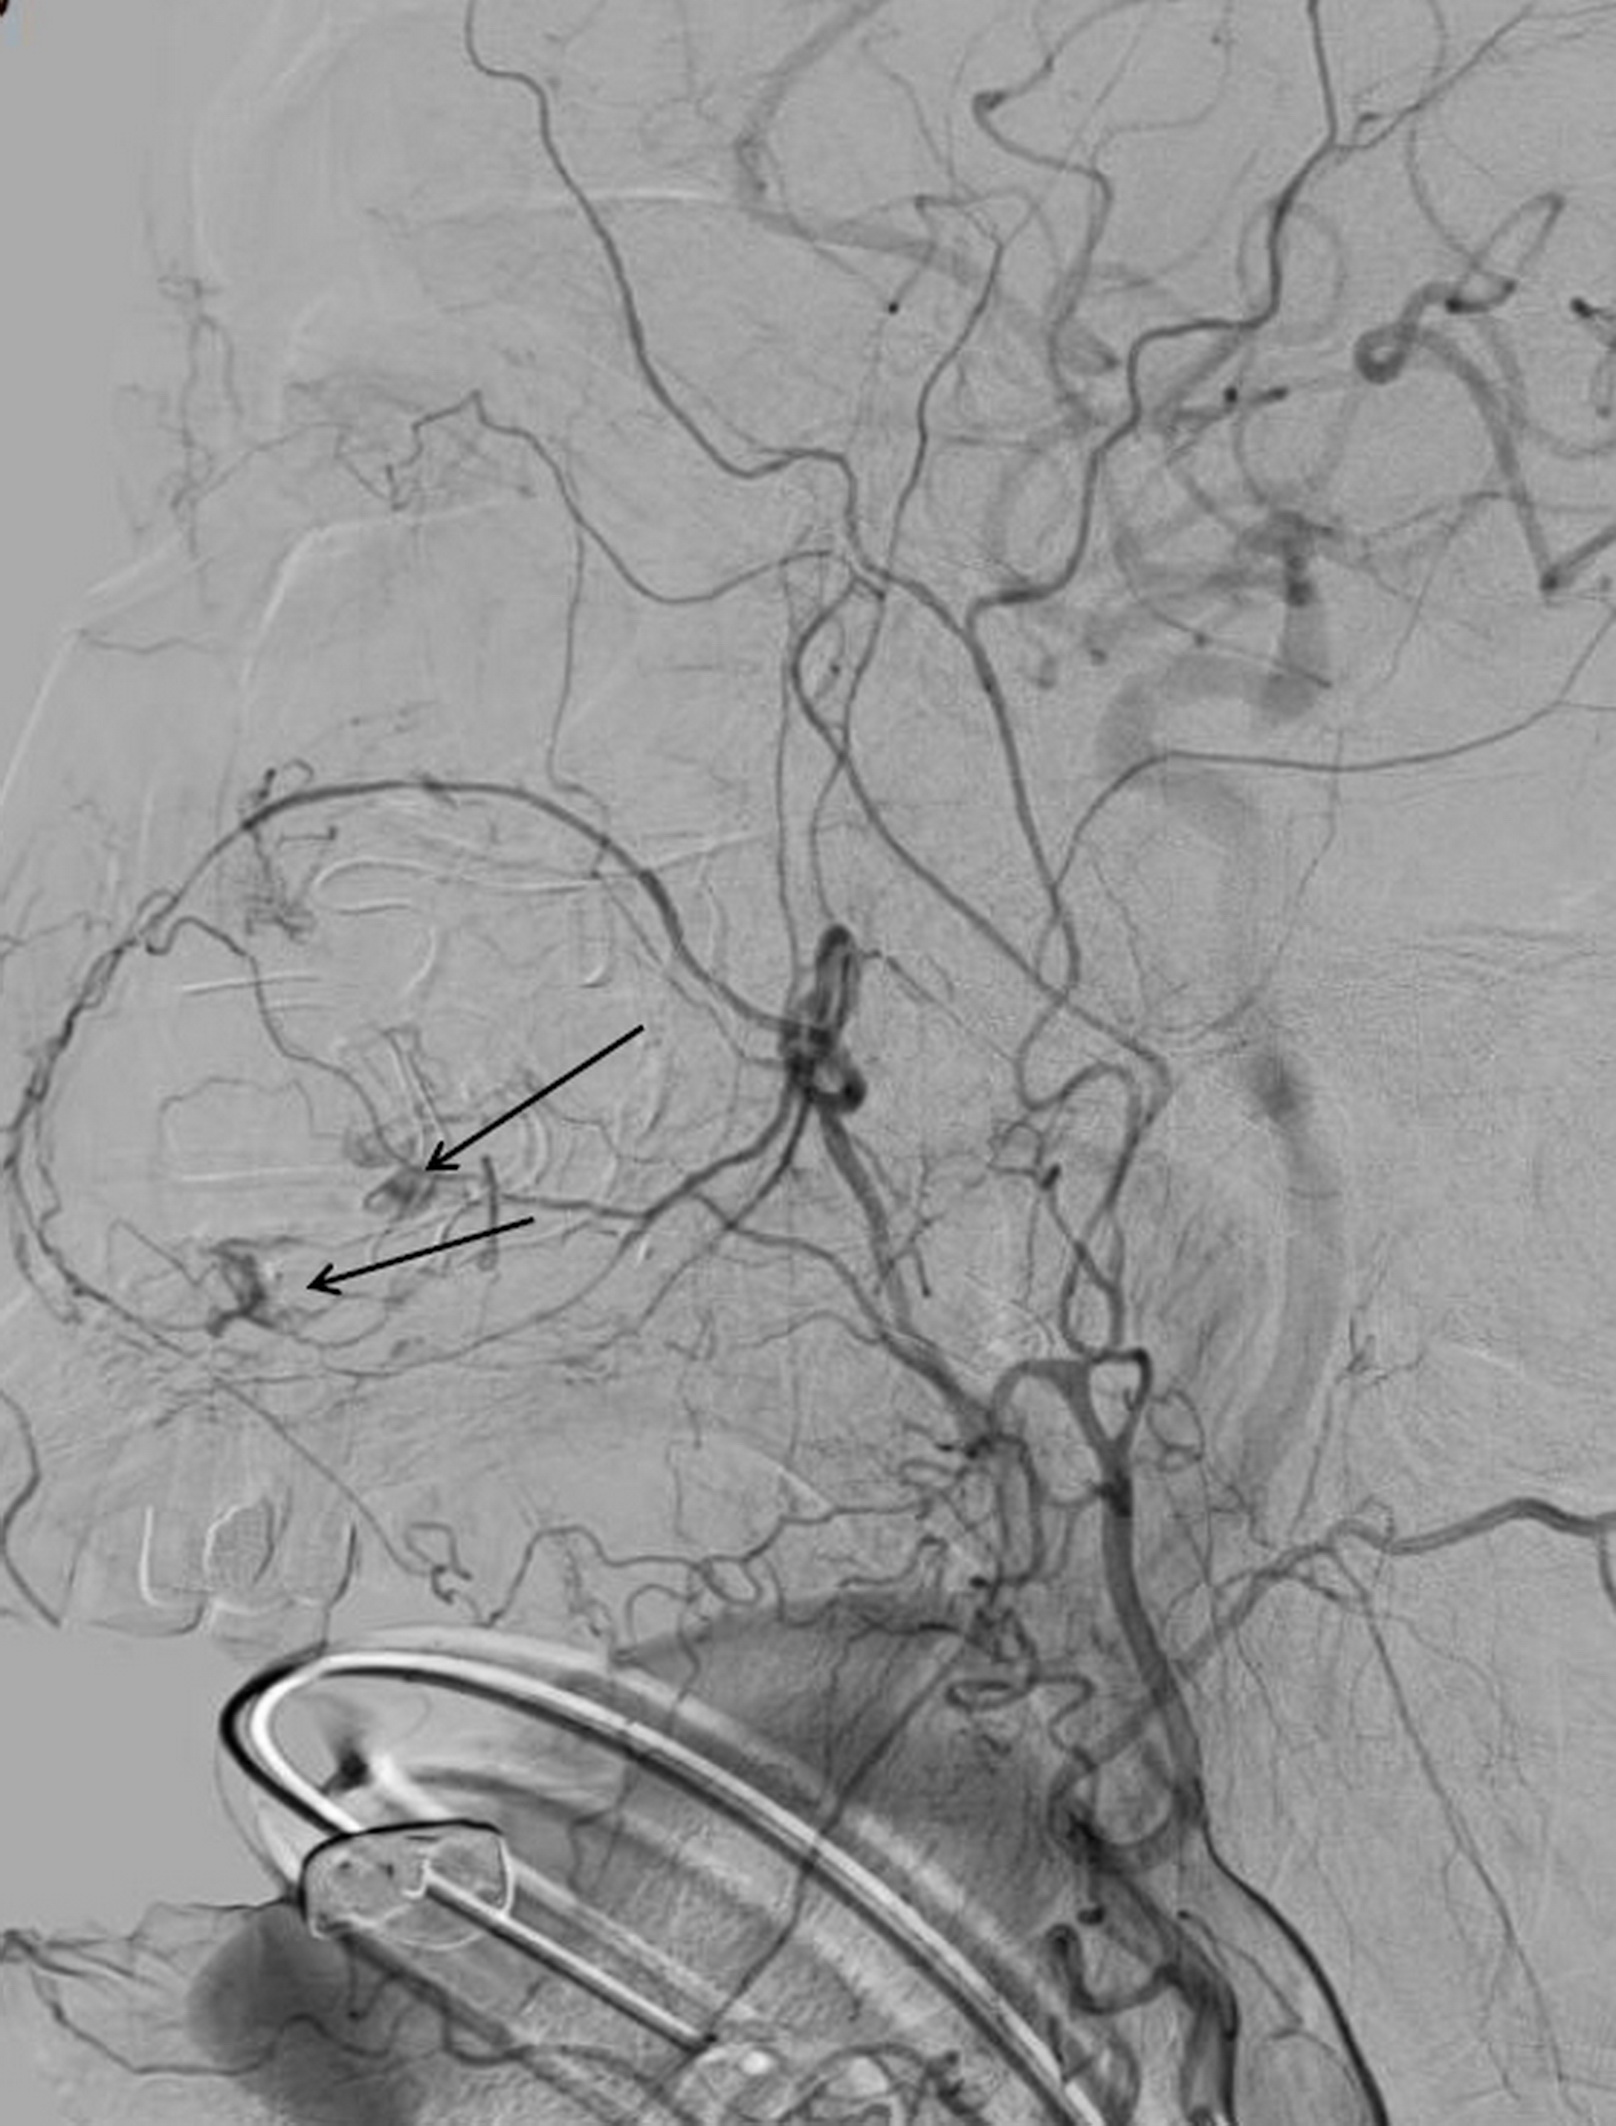

沈炳宏表示,假性動脈瘤屬於血管病變,必須從內部根源去處理病灶,由影像醫學部暨醫療副院長嚴寶勝施行「動脈血管栓塞治療術」,成功阻斷了病灶的血液供應,術後復原良好,鼻腔不再出血,呼吸恢復順暢。